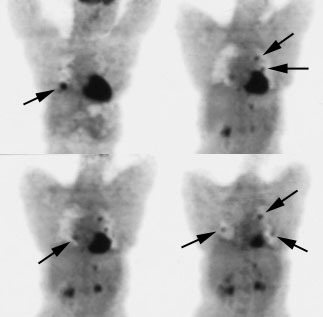

Thyroid Cancer

I-131 scanning has been the mainstay for the evaluation of recurrent thyroid carcinoma.Patients who are found to have I-131 accumulating local recurrences or metastases on diagnostic scans will usually receive subsequent therapeutic I-131 doses which may be curative. Unfortunately, not all recurrences are iodine avid (50-60% of papillary and 64-67% of follicular cancer recurrences are iodine avid).

August 28, 2001